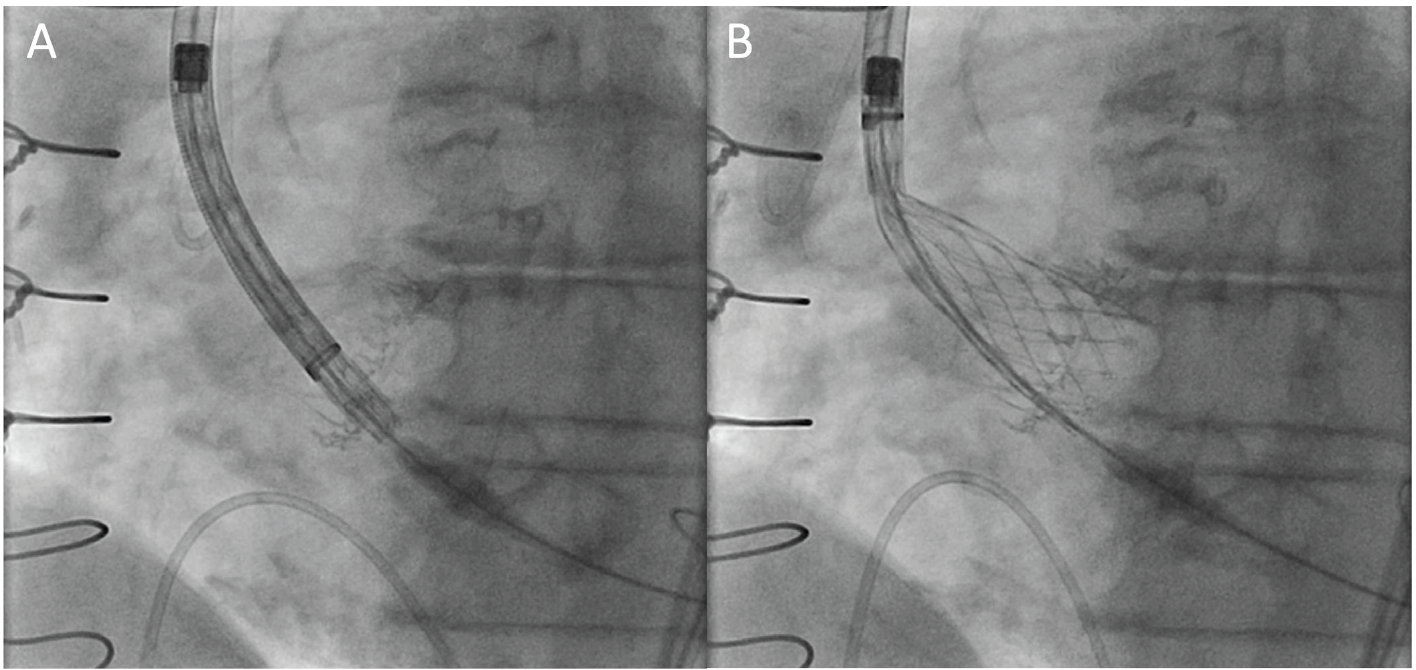

During the TAVR procedure, coplanar angle estimated from preoperative CT scan was easily adjusted referencing the line of Cor-Knot in her aortic annulus without administrating contrast although poor radiodensity from the Trifecta valve. In the coplanar view, the TAVR valve depth was well appreciated in reference to the Cor-Knot line and the TAVR valve was deployed under controlled pacing without contrast use (Figure 1 and Figure 2). We achieved mean aortic pressure gradient of 9 mm Hg without perivalvular leakage or conduction abnormalities. She was discharged to home the next day without renal injury.